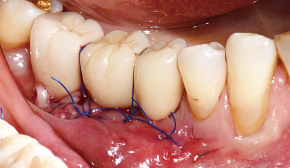

터널 테크닉 시 : 터널 내부에 박리 된 공간으로 깊숙이 골이식재 전달

4. Bone Carrier를 골이식부에 삽입

5. 골이식재 주입

6. 봉합

7. 1차 봉합